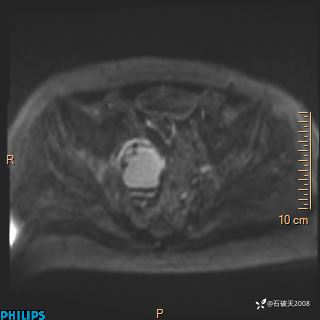

2023年3月份MRI影像

增强轴位